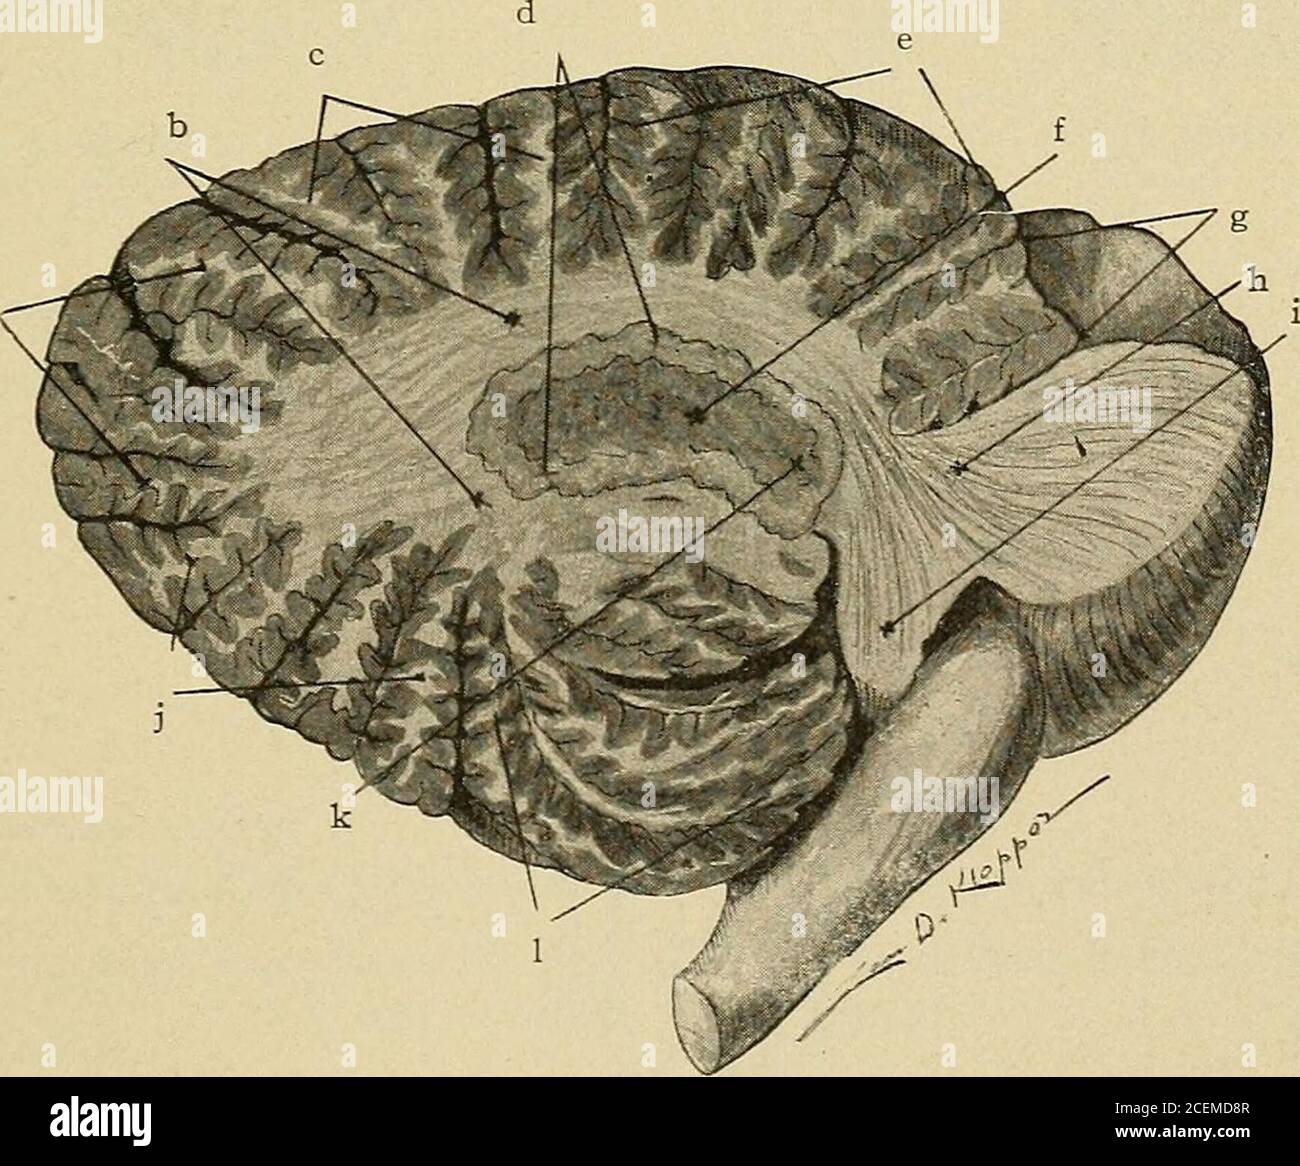

RM2CEMD8R–. Erkrankungen des Nervensystems : für den Hausarzt und Studenten. Abb. 37. – Median Section of Cerebellum, Pons and Medulla. (Santee) a. Predeclivil sulcus, B. Arbor vita?, c. Dekreve monticuli. d. Postdeclivil sulcus, e.Folium vermis. /. Horizontaler Sulcus, g. Knollenvermis. /;. Postpyramidensulcus, i.Pyramid, j. Prepyramidaler Sulcus, k. Uvula. I. Cummen monticuli. m. Postzentralem Sulcus.n. Zentral gelegenes Hotel. 0. Inferiorer Colliculus of corp. quad. P. Cerebral Aqueduct, q. Precentralsulcus, r. Superior medullary velum, s. Lingula. t. Mediales longitudinales Bündel, u. Fasti-gium. v. inferior med